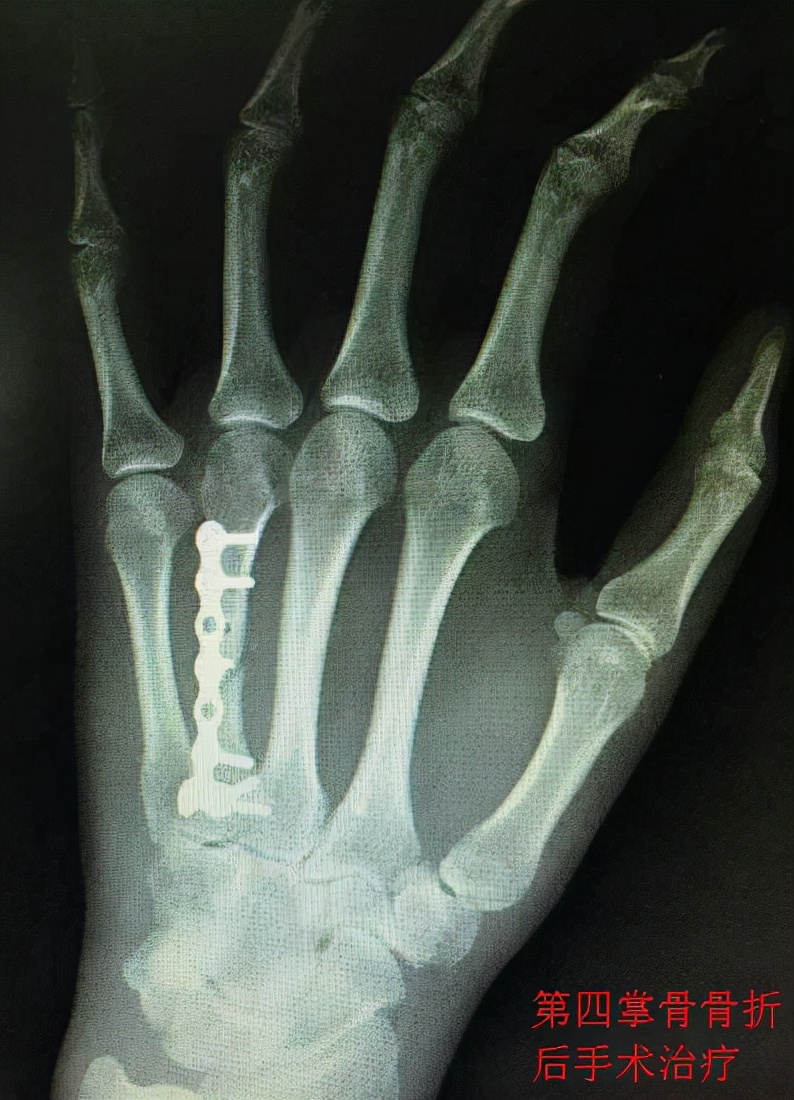

手术治疗 骨折后的手术治疗,通常是指切开复位内固定术,即:将骨折处的软组织切开、分离,将血管、神经等组织剖析、梳理、结扎......在肉眼可见的情况下将断骨复位,再利用坚固的材料(例如钢钉、钢丝、钢条、接骨板、克氏针等)使断骨固定,最后再将其他组织逐层复位、缝合的过程。手术治疗可以最大程度地确保骨折的复位和固定,但却会对皮肤、肌肉、血管、神经等组织造成不同程度的切割伤。无论是掌骨骨折还是指骨骨折,如果骨折后难以复位,或者复位后因为复杂的力学关系难以保持稳定,就要果断实施切开复位内固定手术(也有一部分患者可以实施微创术)。需要实施手术治疗的掌骨和指骨骨折主要包括骨干和骨颈部分的斜形骨折、螺旋形骨折和粉碎性骨折,还包括开放性骨折、移位较多的关节内骨折、不稳定的骺板分离(骺板:骨骺与骨干之间的连接部)、韧带附着处撕脱型骨折、闭合性多发掌骨骨折(非重大外力导致的骨折,多存在骨折自身病变)、骨折脱位(骨折与关节脱位并存)、远节指骨掌侧基底部骨折、骨折块较大的远节指骨背侧基底部骨折等。